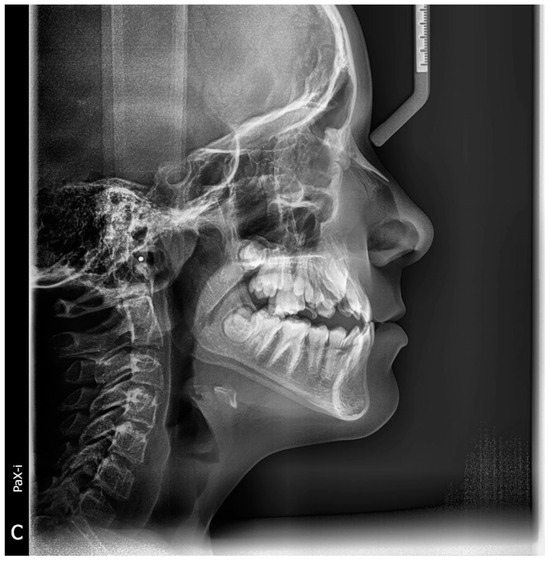

2.3.1. Reading Images

2.3.2. Preprocessing Step